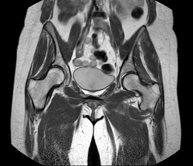

- Hip MRI

Examination for the study of injuries to tendons, muscles and hip joints. Enables early detection of hip osteoarthritis. It is very useful for detecting bursitis and dynamic osteopathy of the pubis, which is common in athletes. It lasts approximately 20 minutes. It is a radiation-free procedure.